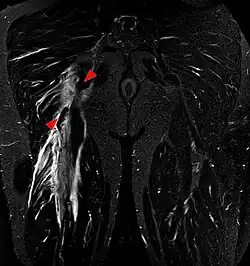

Imaging

Imaging the hamstring muscles is usually performed with an ultrasound and/or MRI.[9] The biceps femoris is most commonly injured, followed by semitendinosus. Semimembranosus injury is rare. Imaging is useful in differentiating the grade of strain, especially if the muscle is completely torn.[10] In this setting, the level and degree of retraction can be determined, serving as a useful roadmap prior to any surgery. Those with a hamstring strain of greater than 60 mm (2.4 in) in length have a greater risk of recurrence.[11]